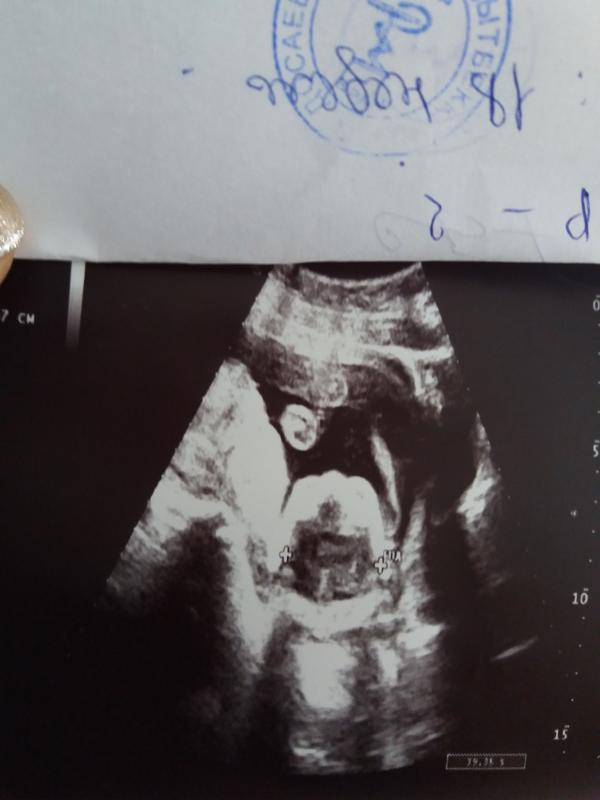

Сегодня ходили на узи)) пол попросила написать на бумаге) так и не посмотрев отдали кондитеру)) будет тортик, завтра только теперь узнаем!))) Очень интересно, кто же там??)